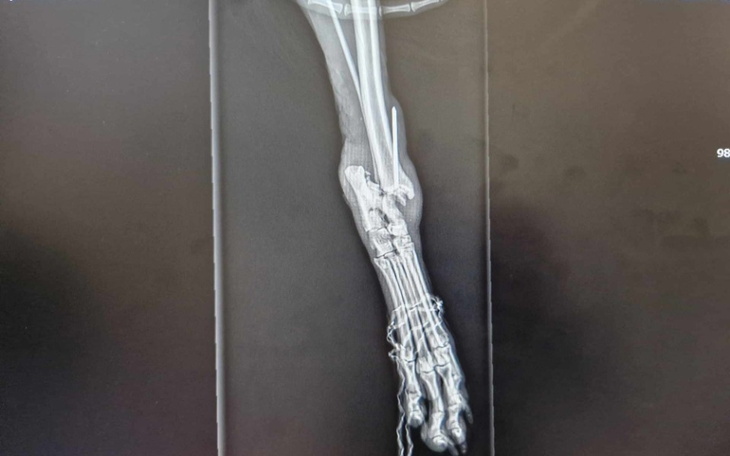

Niestety stan łapki jest tragiczny!Rana była z ogromnym stanem zapalnym.

Obecnie jest oczyszczona.Wyciągnięty ze środka połamany gwóźdź,który prawdopodobnie miał scalać złamanie.

Miluś dostał leki na dwa tygodnie ,aby zmnirjszyć stan zapalny .Po tym czasie czeka go albo reoperacja albo amputacja łapki.